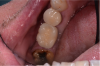

In this case, the patient’s right maxillary first molar had been extracted, and the site was grafted. The periapical radiograph taken after 6 months of healing indicated the presence of dense bone (Figure 11). There was also ample attached mucosa (Figure 12). Impressions were taken, a diagnostic cast was made, and a wax-up of the restoration was placed in the model (Figure 13). To make the radiographic guide for this case, a silicone putty index was created over the diagnostic wax-up, as described earlier. A panoramic radiograph and a CBCT scan (Figure 14) were taken with the radiographic guide in place; the guide post in the index can clearly be seen.

After merging the digitized cast and CBCT scan data, the dimensions of the site were evaluated. Almost 11 mm of bone was present below the maxillary sinus, and the width of the site was 8.5 mm, which was sufficient space to enable creation of a screw-retained restoration. To facilitate the screw access, a decision was made to position the implant slightly lingually, while maintaining the implant within the housing of buccolingual plate.

Fig 12. Sufficient attached mucosa was evident after 6 months of healing.

Figure 12

Fig 13. Diagnostic wax-up of tooth No. 3 restoration placed in model.

Figure 13